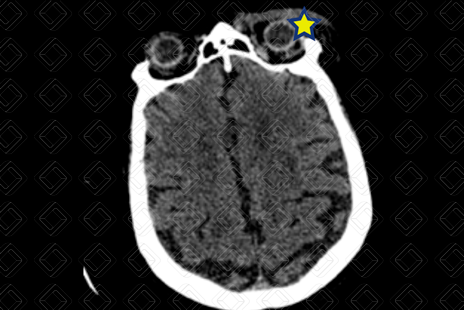

Texto alternativo para a imagem Figura 3. Créditos: Dra. Elazir Mota - Rio de Janeiro/RJ

Descrição da lesão: Tomografia computadorizada de crânio. A umento das partes moles extracranianas na região frontal e periorbitária esquerdas (asteriscos), caracterizando hematoma subgaleal. Não há extensão intracraniana ou sinais de fratura.

Hematoma subgaleal: A umento extracraniano das partes moles, sem extensão intracraniana. Em geral, ocorre por ruptura de veias emissárias que drenam o couro cabeludo, com acúmulo de sangue entre periósteo superficial e aponeurose do músculo do couro cabeludo.